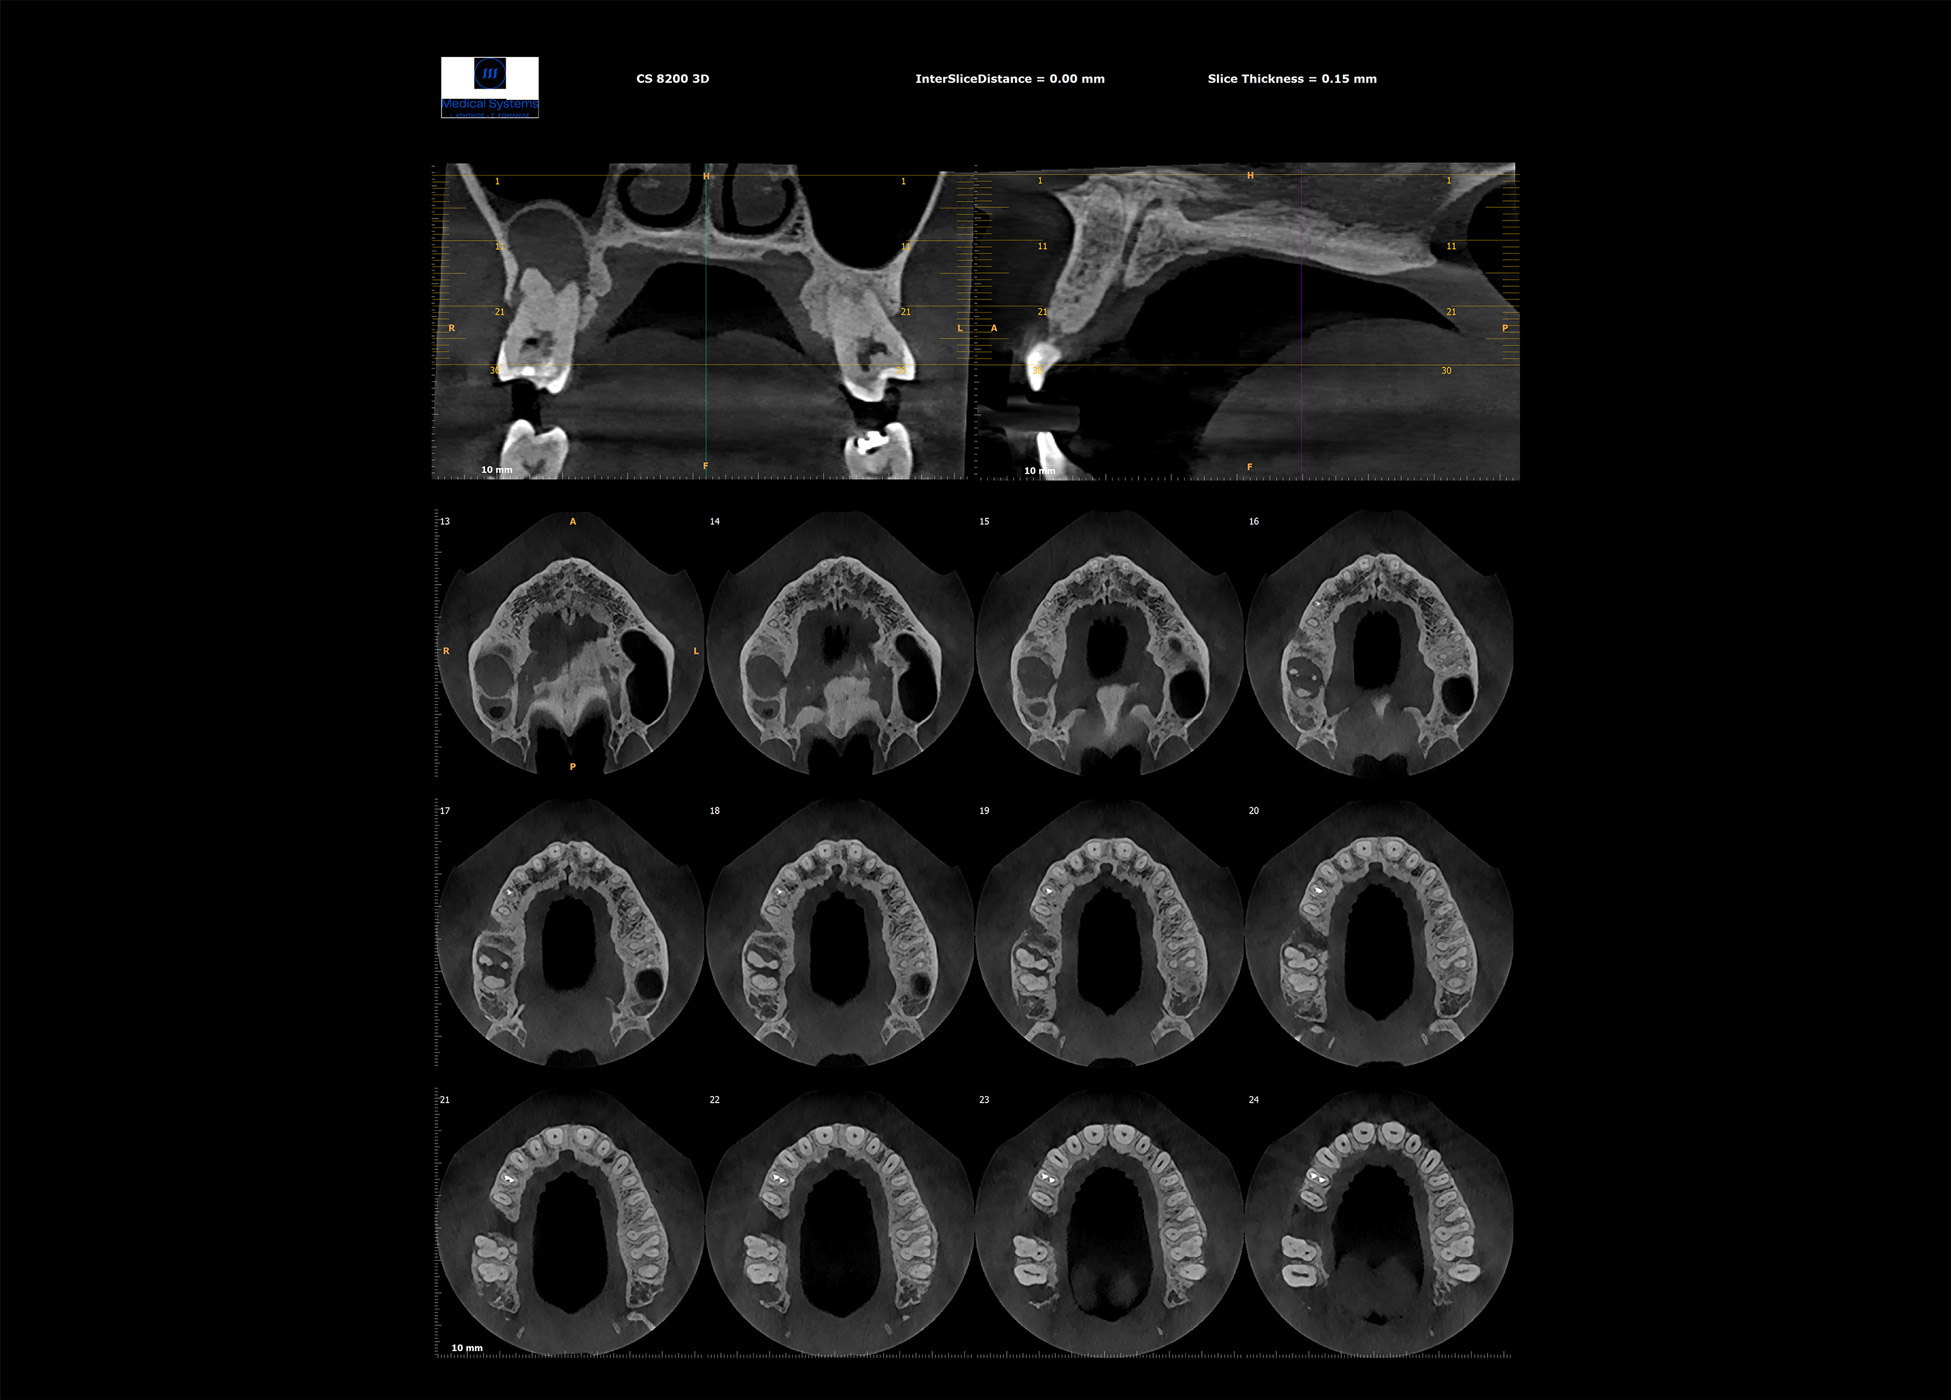

Ογκομετρικός Τομογράφος

- Oγκομετρικό τομογράφο – CBCT (3D) πολλαπλών οπτικών πεδίων, αξεπέραστης ποιότητας εικόνας.